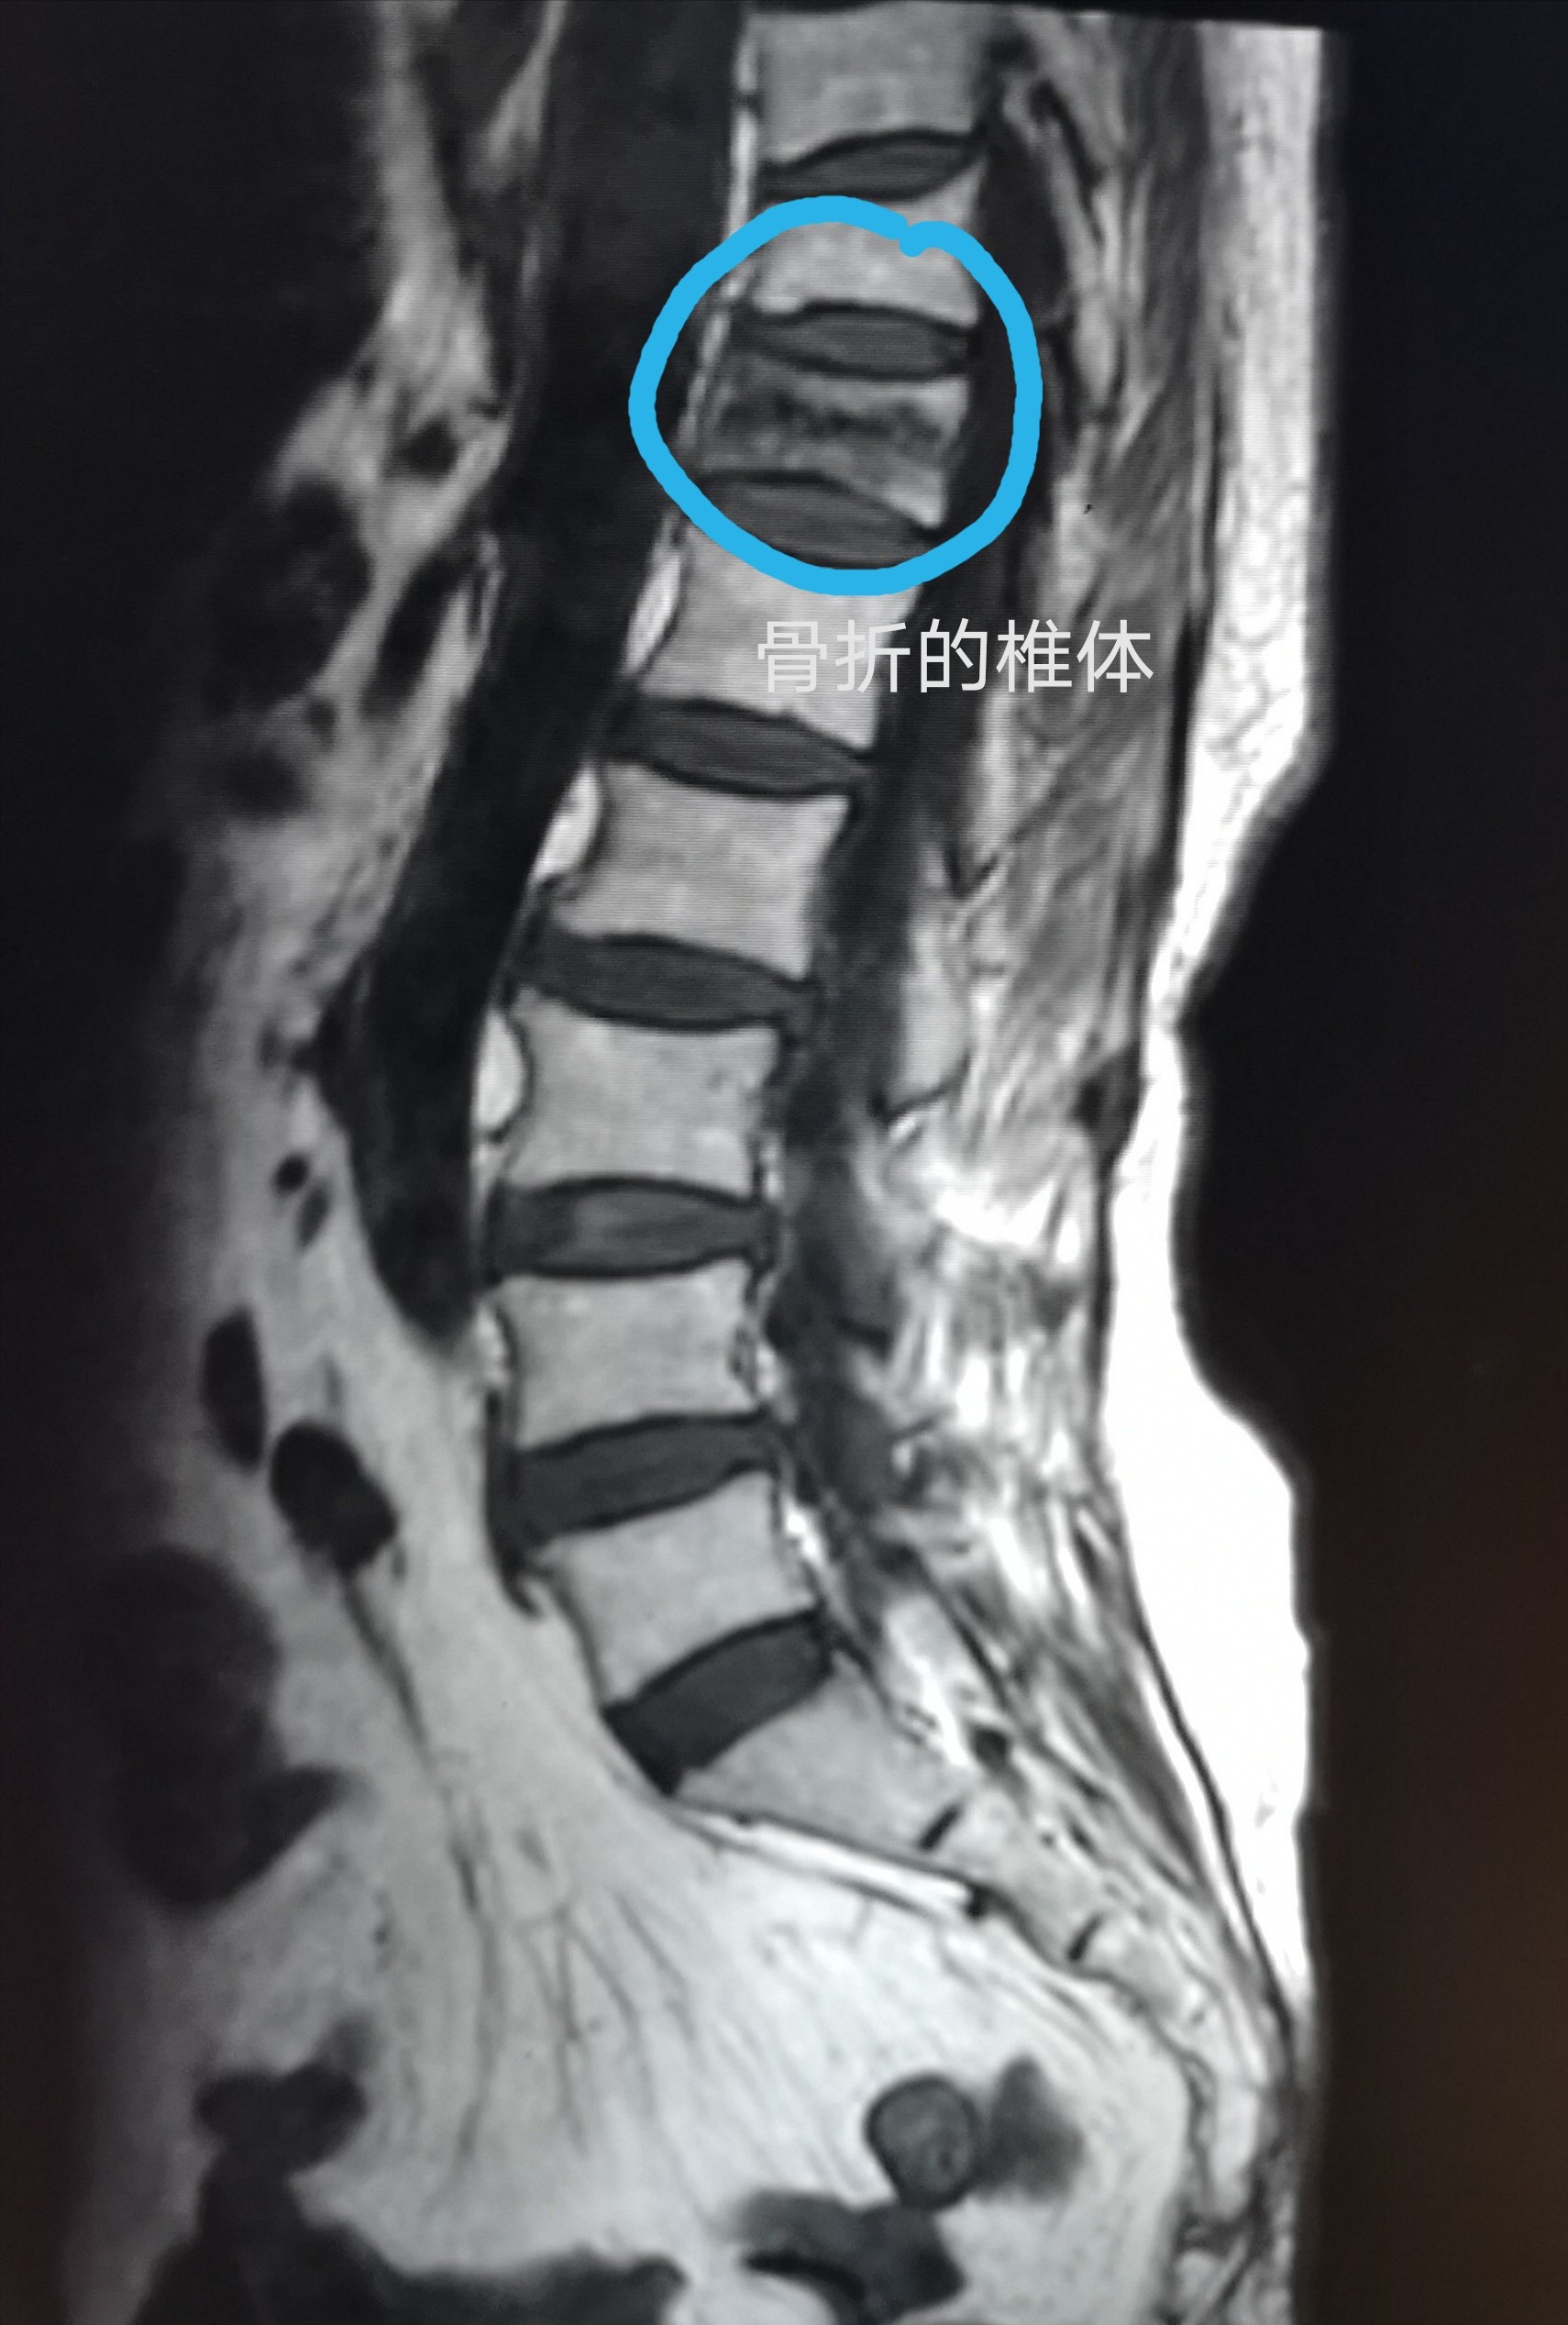

发生了脊柱压缩性骨折,如何治疗?

t11---l1椎体 压缩骨折 椎体成形术后两个月腰痛

术前x线平片示腰2椎体明显压缩骨折,压缩约1/2.